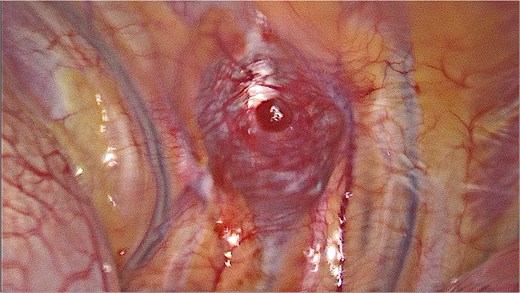

It was decided to remove the lesion using video-assisted thoracic surgery. The moderately firm mass under the parietal pleura in the ninth intercostal space was identified (Fig. 3). The tumor with the additional intramuscular portion of it was radically removed.

Video-assisted thoracic surgery. Intraoperative view of the tumor.